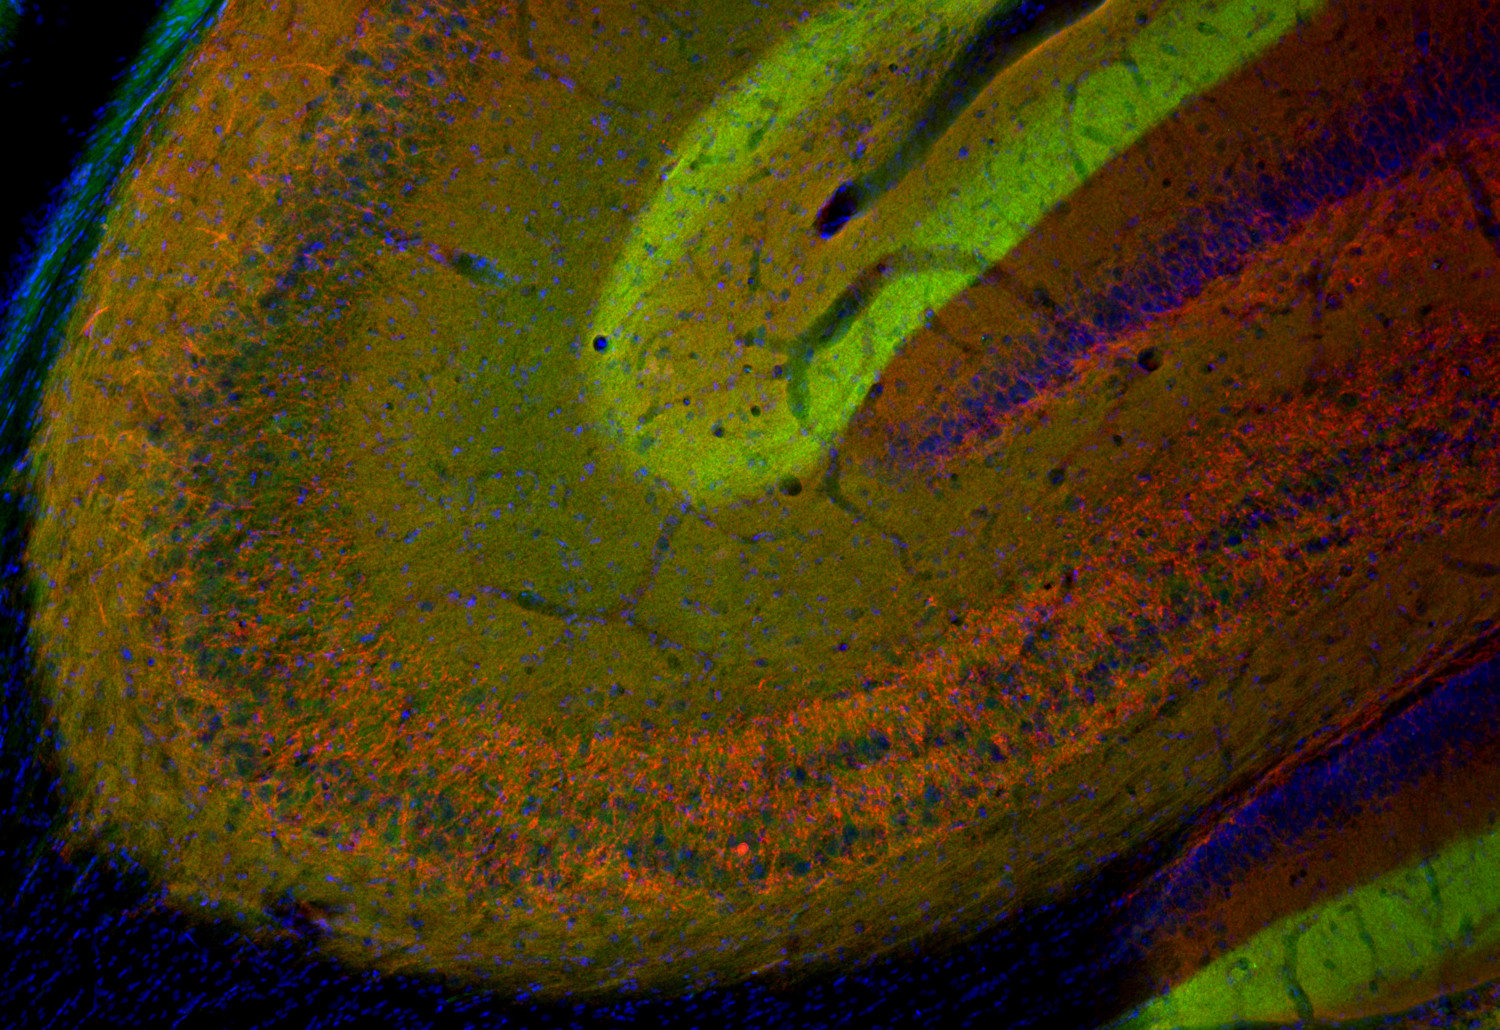

70386-2/asset/392a6bc4-3dab-4838-82e2-d7134cbd4082/main.assets/gr2_lrg.jpg)